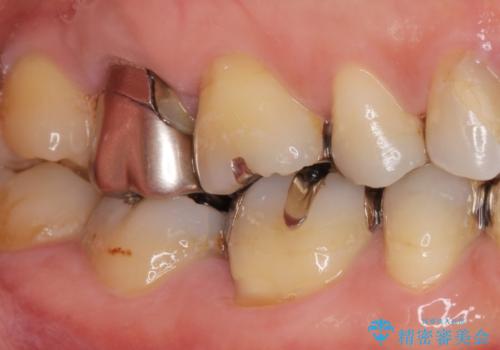

精査したところ、右上の奥歯(右上7)はう蝕が深く骨吸収も進行しており保存不可能な状態でした。

金属アレルギーの疑いがあり、インプラントも避けたいとの患者様のご希望により、親知らずを移植することにしました。

移植がうまくいかない可能性を考慮し、ブリッジもできるよう隣の親知らず(右上8)は残し、反対側の親知らず(左上8)を移植しました。